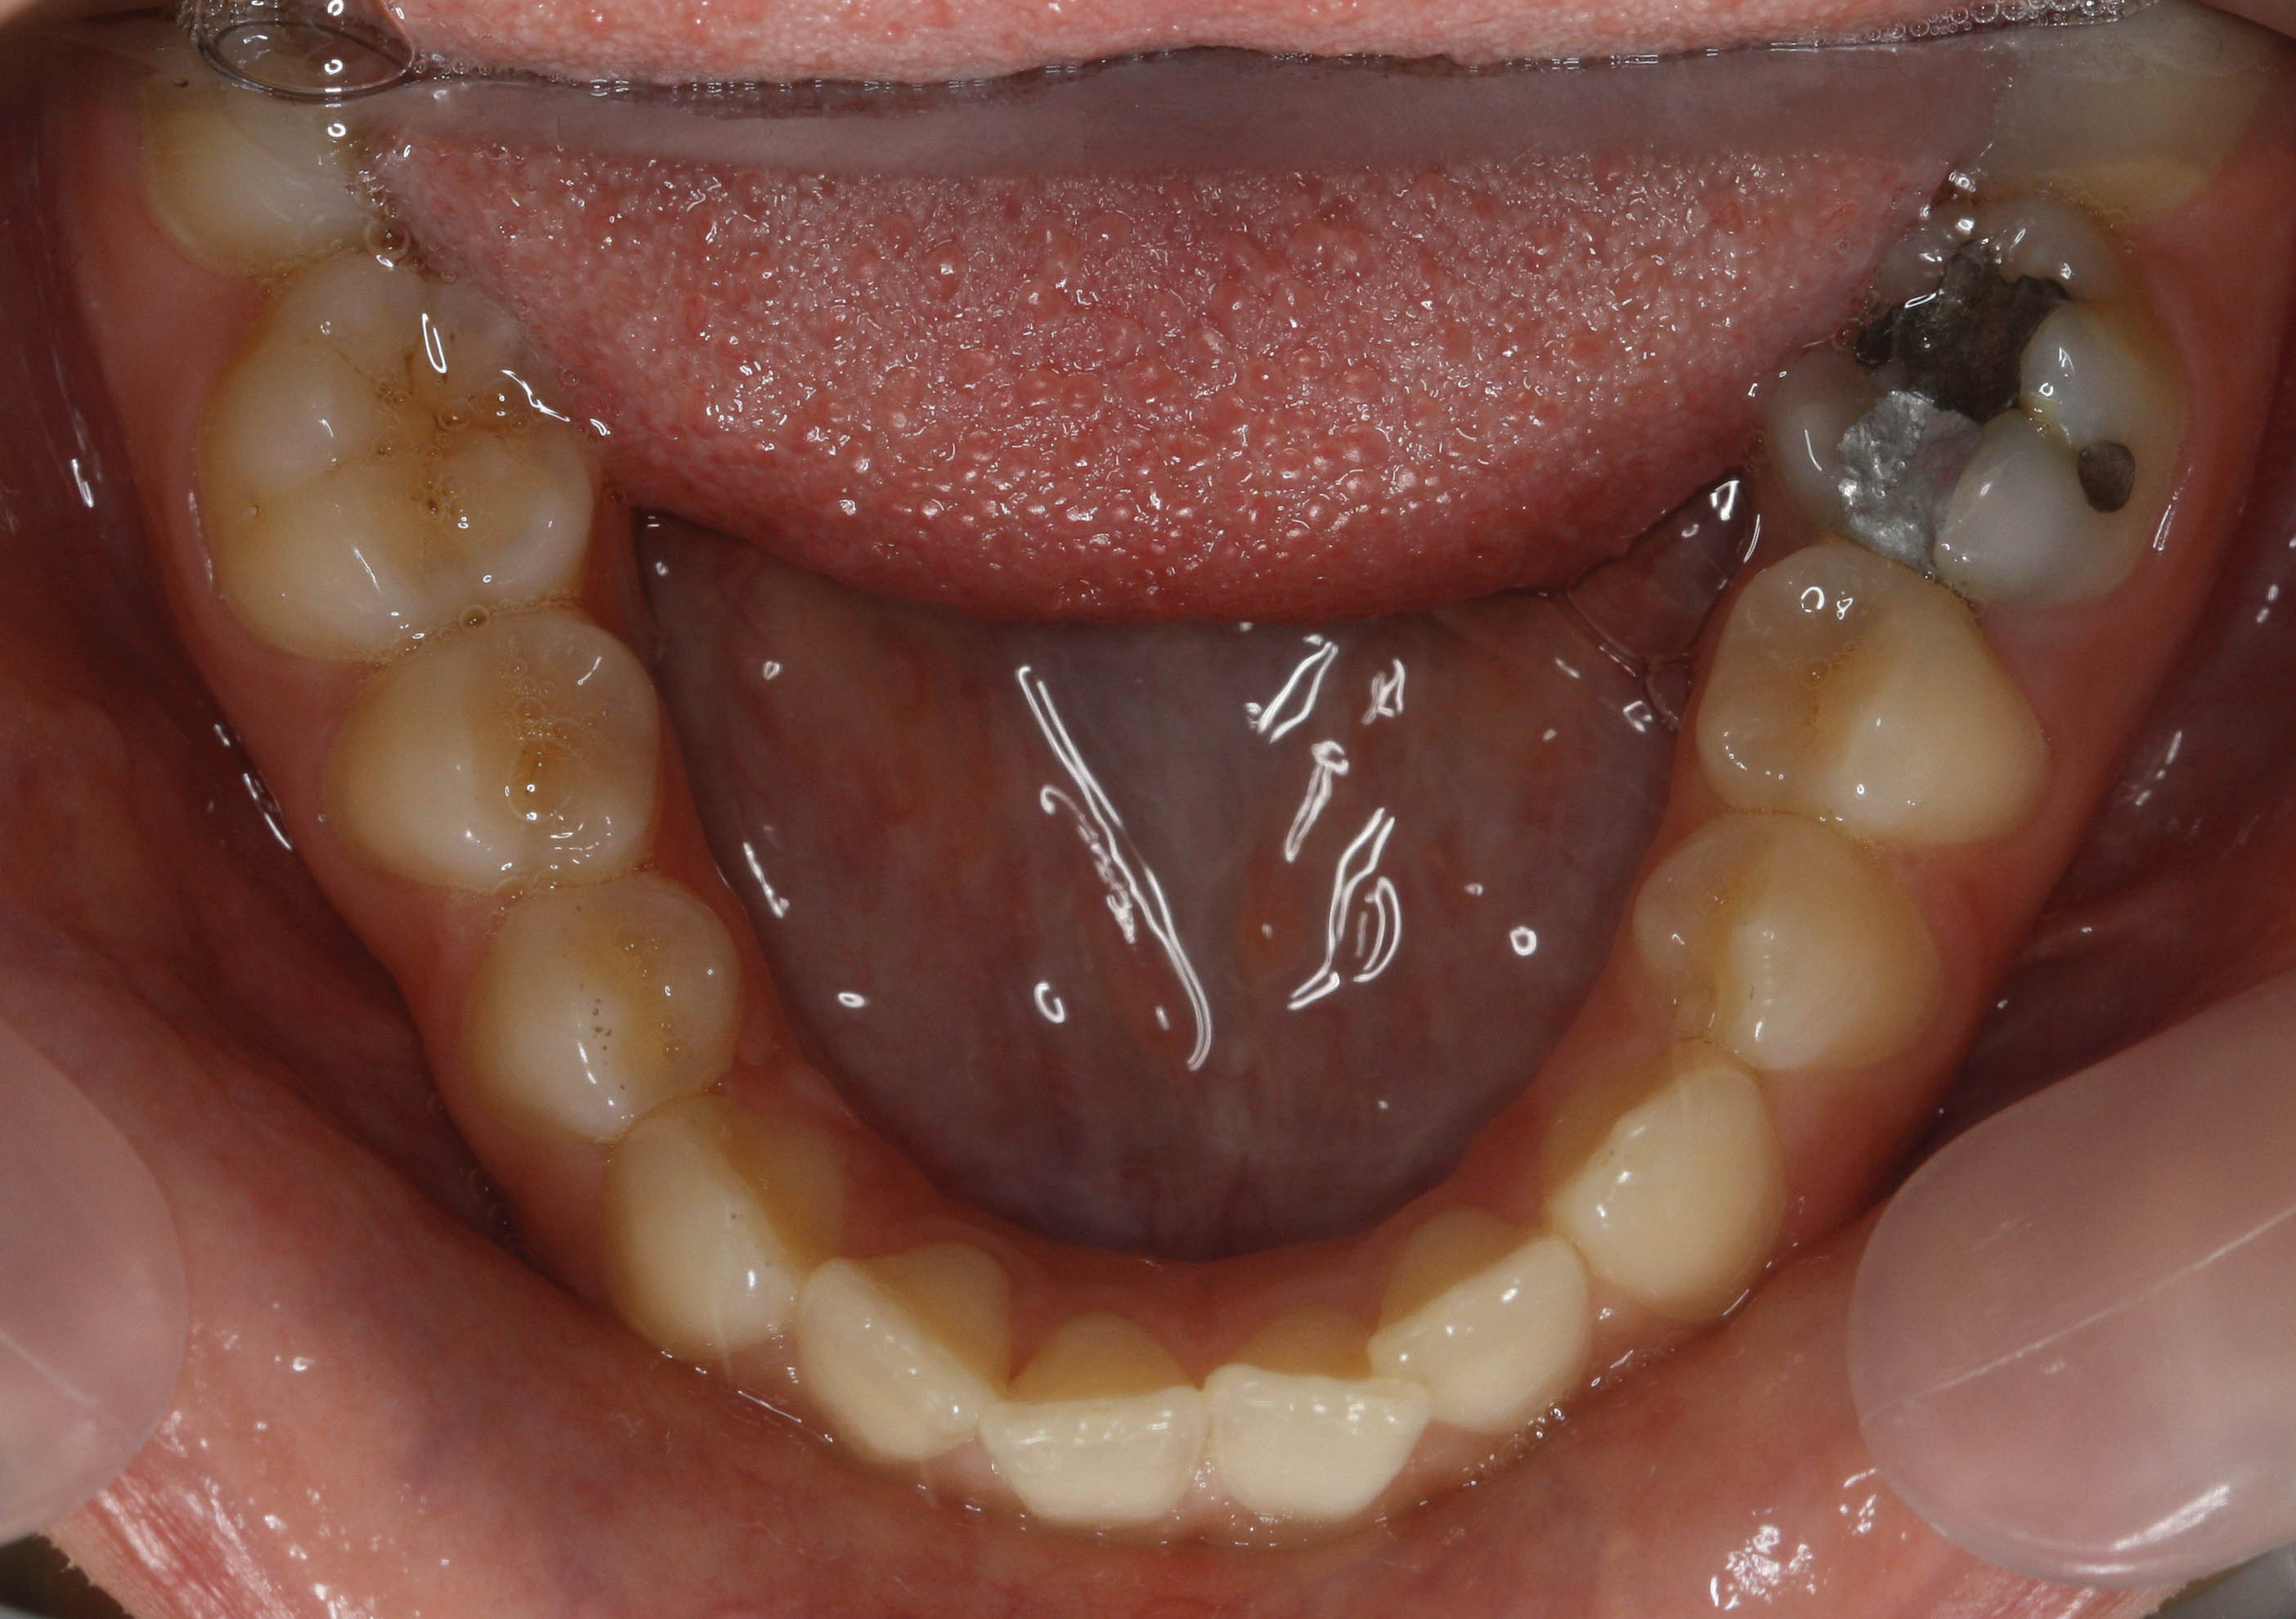

اگر كمبود فضا جزئی باشد (شکل 200-1) دندانهای کانین تا کانین را استریپ کنید. در این حالت حدود 3mm در كل قوس فكی فضا بدست میآید (1.5mm در هر طرف). نیازی به پالاتال بار و لینگوال آرچ ندارید.

شکل 200-1: کمبود فضای جزئی